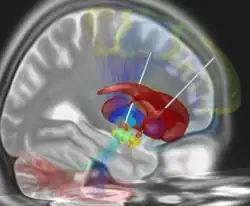

La stimulation cérébrale profonde est un traitement médical invasif (neurochirurgical) consistant à implanter chirurgicalement dans le cerveau des électrodes, connectées à un boîtier mis en place sous la peau et qui délivre un courant électrique de faible intensité dans certaines structures spécifiques situées en profondeur de cet organe comme le thalamus ou certains noyaux des ganglions de la base, comme le noyau sous-thalamique ou le globus pallidus. Les sites stimulés varient selon l'indication : Ce traitement peut en effet être utilisé pour traiter des maladies neurologiques, telles que la maladie de Parkinson, les tremblements ou les dystonies, mais aussi plus rarement des troubles psychiques résistants aux autres formes de traitements, tels que des formes sévères de TOC ou de dépression.

La cible peut être le noyau sous-thalamique ou le globus pallidus, les deux sites étant équivalents du point de vue de l'efficacité[8]. Elle peut être unilatérale ou bilatérale en cas de résultats insuffisants[9].